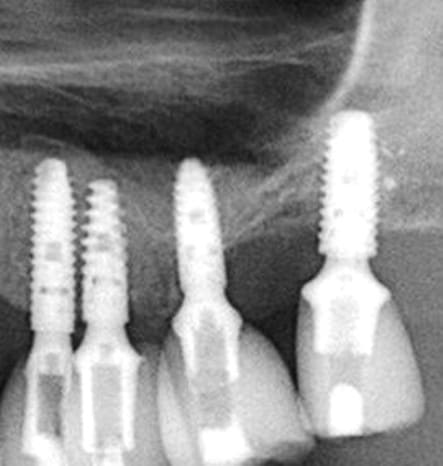

je reprends le sujet 26, car il est certain que ça ne rentre pas dans la logique du soulevé de sinus, mais que l'abord latéral aurais été plus sur.

et pourtant le résultat ne me déplait pas(entre septembre 2015 et Mars 2016)